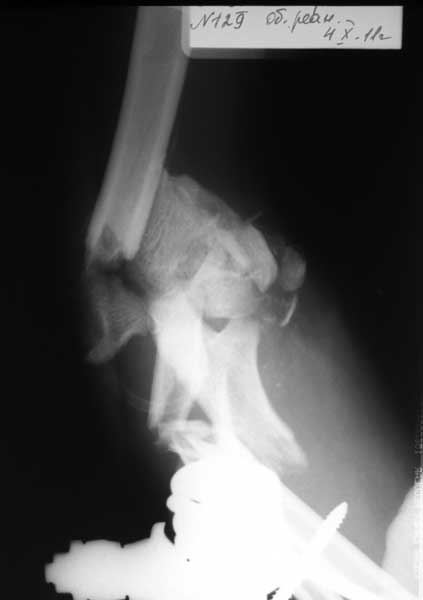

Re: тяжёлое повреждение локтевого сустава

Прошу простить за задержку - не было линии. Шлю снимки.